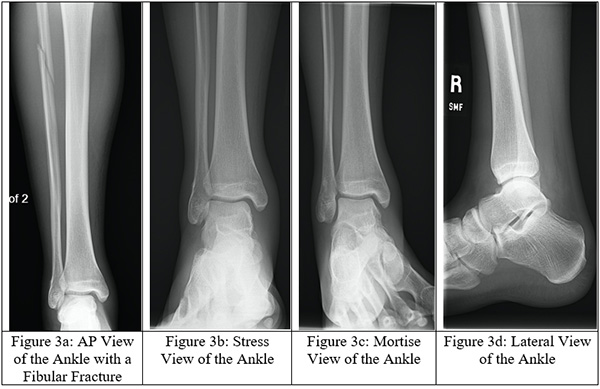

Obtaining images at the initial visit is important to rule out a Maisonneuve fracture. Plain radiographs are vital as they can identify fibular fractures, fibular shortening, and any abnormal spacing between the tibia and fibula caused by syndesmotic disruption. Traditionally, ankle radiographs are taken in anterior-posterior (AP) view, stress view (abduction and external rotation), mortise view, and lateral view (Figures 3a-d). It is necessary to acquire AP and lateral radiographs of the knee with tibial and fibular views to determine the extent of the fibular fracture (Figures 4a-b). When reviewing the radiographs, it is important to measure the tibiofibular clear space, medial clear space, and tibiofibular overlap. The tibiofibular clear space is measured at 1 cm above the talus and measures the distance between the medial border of the fibula and the lateral border of the tibia. Typically, the tibiofibular clear space is less than 5-6 mm on the AP and mortise views. Anything greater than 10 mm is diagnostic of a syndesmotic injury.